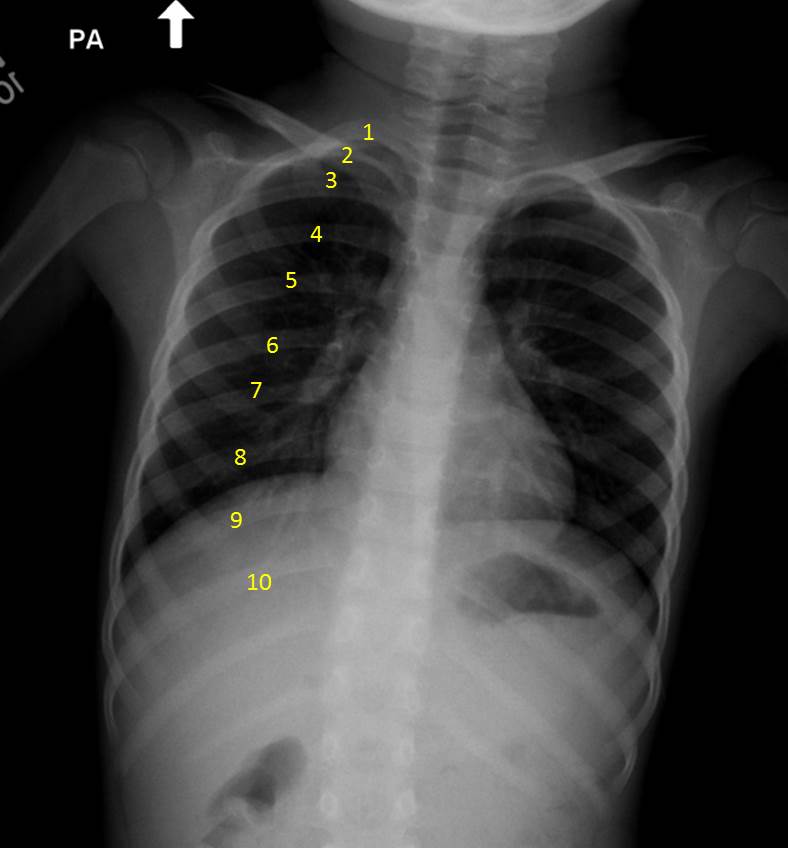

Chest X-ray, Normal, PA

The right posterior ribs are numbered.   The right diaphragm is nearly even with the 8th rib.